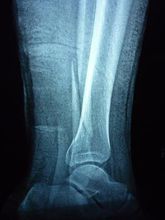

踝骨骨折

踝骨骨折會局部腫脹,壓痛和功能障礙。診斷時,首先應根據外傷史和臨床症狀以及X 線片顯示的骨折類型,分析造成損傷的機制。創傷性關節炎。